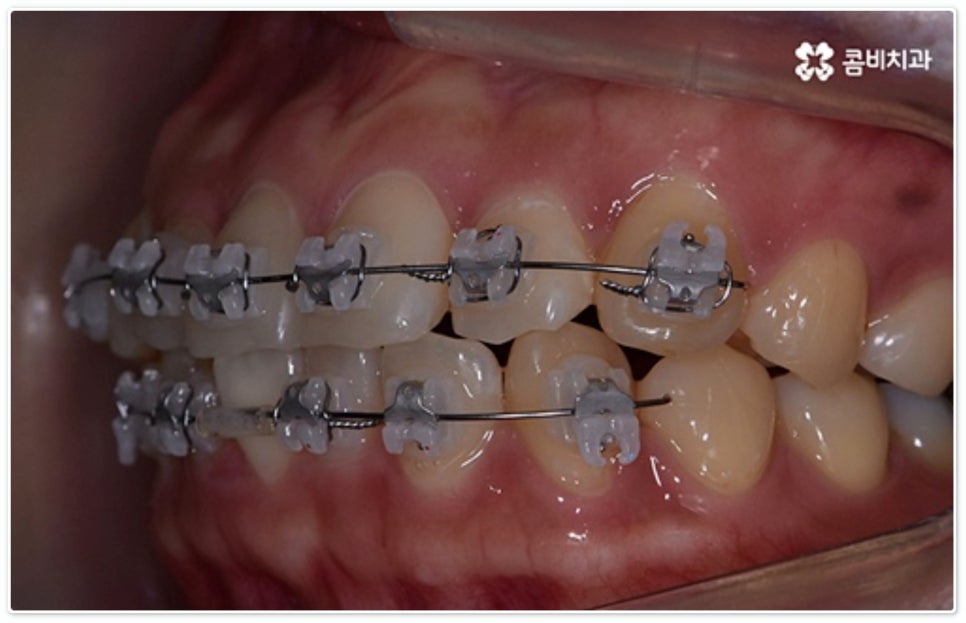

그렇지 않고 전후방 각도 조절 또는 단순 횡적인 움직임으로 치열 개선이 가능한 케이스는 부분 교정을 진행하는데, 사진에서 보시는 사례가 바로 그런 경우에 속하고 있습니다. 앞니 6개에만 브라켓을 부착하였는데 보시다시피 치아 색상과 유사한 세라믹 재질의 장치를 이용하여 심미성 또한 높여 주었음을 알 수 있어요.

토끼 앞니, 나비 앞니 중 이와 같이 어금니 교합은 정상이지만 앞니 또는 일부 치아가 돌출되거나 방향이 틀어진 경우 뿐 아니라 다른 치료 (보철 치료나 임플란트 시술) 를 위해 먼저 부분적으로 치아 이동이 필요한 경우, 교정 치료를 받은 적이 있으나 앞니 또는 주변 치아 배열이 다시 틀어진 경우 등에 있어서도 부분 교정이 이용될 수 있습니다. 그러므로 ‘치료가 오래 걸릴 것이다’, ‘장치가 보이는 게 많이 부담스럽다’, ‘재교정을 받는 것이 무섭다’ 등등 여러 걱정으로 교정 치료 시기를 미루시지 말고 필요한 경우 상담부터 차근차근 진행해 보시면 좋을 거예요.